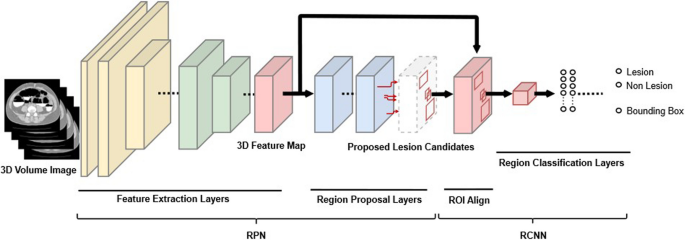

Explanation of the AI algorithm. Neural network architecture

During this study, we adopted a neural network structure [19, 20] that was designed based on the faster R-CNNs [21] (Fig. 3). The neural network was composed of two main subnetworks: region proposal network and region-based CNN. During the first stage, the region proposal network approximately detected lesion candidate regions in the input image and was composed of “feature extraction layers” and “region proposal layers.” IoU is an index that is calculated by using a bounding box that is delimited as the smallest rectangle of the lesion inferred by AI and a correct-answer bounding box that is delimited with the smallest rectangle of the correct lesion (ground truth annotated as the correct answer) in order to calculate the degree of intersection between the rectangles as follows.

Overview of the structure of the detection network. “Feature extraction layers” extracted features from CT colonography data, which are 3D image data, using 3D convolution. “Region proposal layers” obtained lesion candidate regions from the features. During the second stage, region-based CNNs accurately determined whether each candidate region detected during the previous stage was a target lesion and was composed of “region of interest align” and “region classification layers”. “Region of interest align” resized the features of the detected lesion candidate regions to a fixed size, and “region classification layers” determined whether each lesion candidate region was a lesion. 3D: three dimensional; RCNN: region-based convolutional neural network; RPN: region proposal network.

The input image was resampled with approximately 1.0-mm isotropic pixels. Next, the CT values of -800 to 400 Hounsfield units were normalized as 0 to 1 and input into the network. Separately, the colorectal region was segmented using a large intestine extraction algorithm, and a circumscribed rectangular region of the colorectal region was cut out and input into the network.